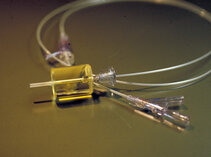

Our research group specializes in molecular and basic science models of clinically relevant topics. Our team is interested, for instance, in developing methods to predict and prevent recurrence of stenotic lesions after catheter interventions.

We have previously evaluated modifications of thrombectomy devices, stents and balloons delivering drugs to the vessel wall, and we have created new methods of ultrasound analysis in vascular medicine.

These images tell a story and we will explain it to you…..